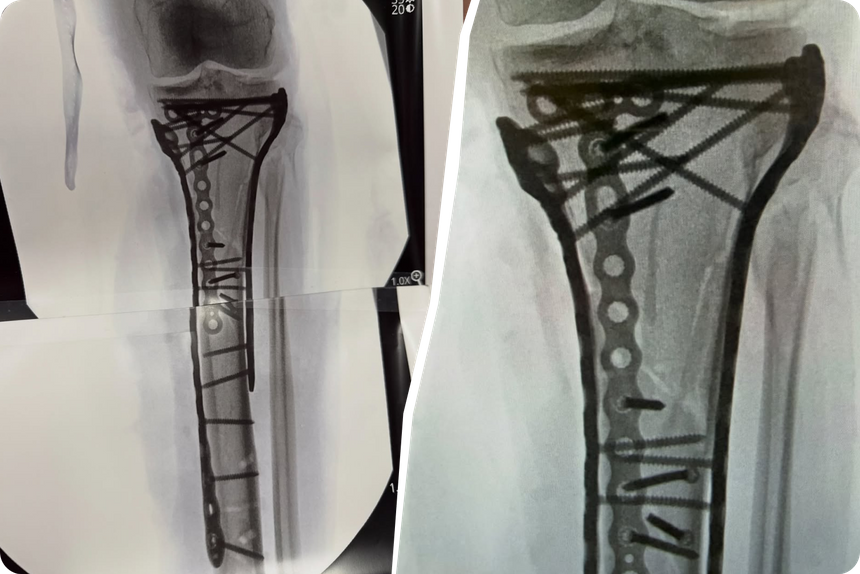

В США спортсменке сделали пятую операцию, которая длилась шесть часов. В ногу горнолыжницы вставили несколько пластин и винтов.

Нога Линдси Вонн